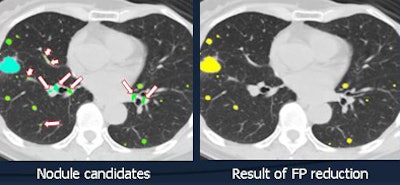

In this experiment, the filter reduced false positives by about 87.1% -- or from 201 per case to 26 per case, Chen said.

![]() |

| False-positive reduction eliminated 87.1% of false positives in 16 cases. Above, a single slice of CT data shows nodule candidates at left and the results of false-positive reduction at right. |